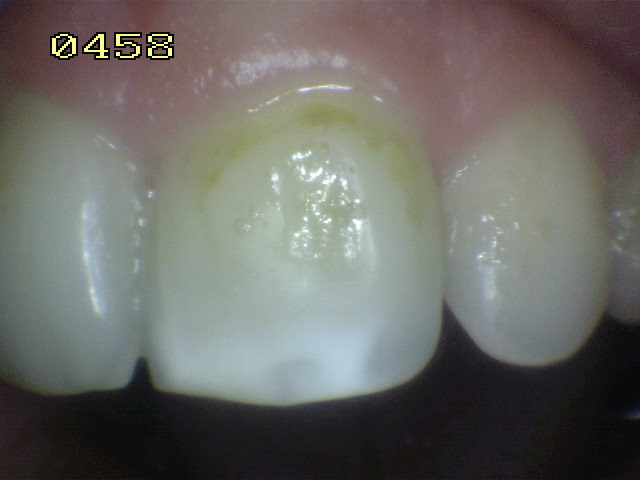

Una mancha oscura de dentina que se observa a través del esmalte intacto,  adyacente a la fosa y reborde marginal,  indica la presencia de desmineralización. (Imagen 0229)

Las Radiografías Bite-Wing son un pre-requisito cuando se considera una restauración con sellador. Éstos no deben mostrar evidencia de caries interproximal que pueden indicar que una restauración deba ser  más extensa. Debe ser considerado que el tamaño real de la lesión es normalmente más grande que la imagen radiográfica. La Transiluminación  también puede ser un beneficio para el diagnóstico de caries oclusal y caries interproximal.